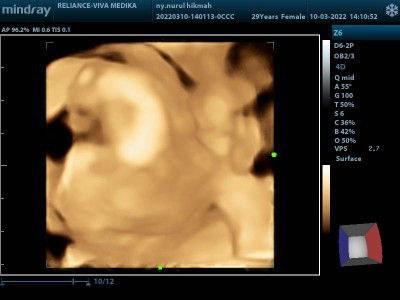

Bund ,mau tanya kalo DJJ 170 usia kandungan 14week aman ga si ya? Karna pas ke bidan bilangnya harusnya djj normal 120-160, emang si aku lg ga enak badan, batuk dan muntah terus, kalo kata bidan nya mungkin karna ibu muntah mulu kurang cairan jd djj Dede nya tinggi, tp kan tetep aja worry ya, ada sepengalaman g? Trus gmn ya cara mengatasi nya??#bantusharing #ingintahu